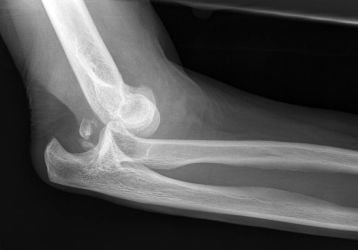

Вывих локтевого сустава: лечение, последствия и первая помощь

Вывих локтевого сустава у детей и взрослых. Способы лечения, оказания первой помощи и предотвращения последствий травмы.

Травма является одной из самых частых причин появления боли в области суставов. Она может быть разной степени тяжести, различаться разной симптоматикой. Человек обычно получает такие виды повреждений: переломы костей или внутрисуставные, ушибы, растяжения, вывихи, разрывы связок. Как бы ни было, они характеризуются болевым синдромом, отеком, повышением местной температуры, ограниченностью подвижности. Причиной травмирования суставов может стать ДТП, бытовое или спортивное повреждение конечности, несчастный случай, сильный удар или падение с высоты. Некоторые травмы могут сопровождаться деформацией сочленений. Какая бы она ни была, больному требуется предварительная иммобилизация конечности, а также последующее лечение. В особо сложных случаях лечение больного производится в стационаре. Для восстановления функциональности травмированных участков понадобится определенный период реабилитации. Длится он по-разному: на это влияет степень тяжести повреждения. Осложнения после травмы бывают достаточно серьезными, поэтому с лечением лучше не затягивать.